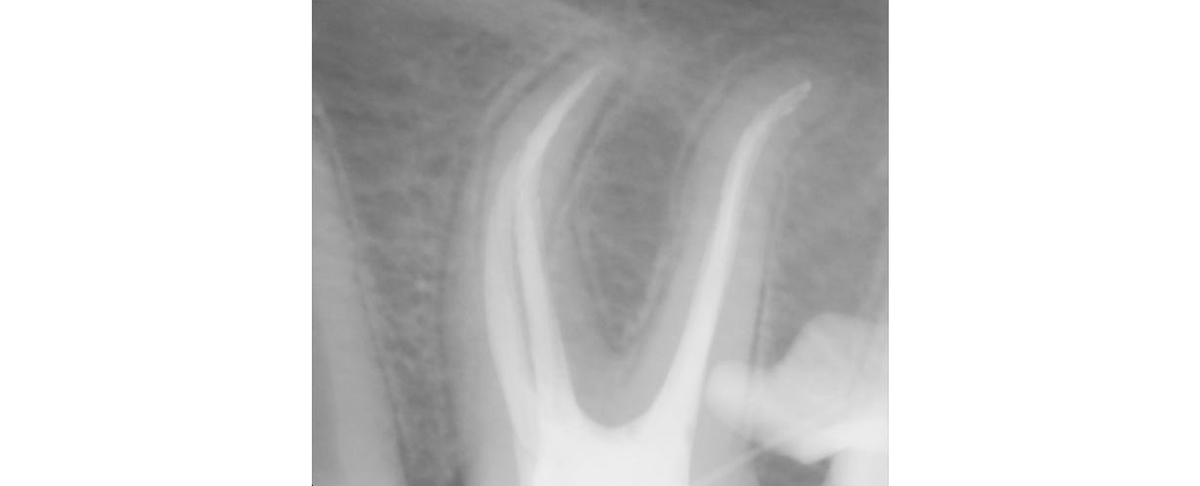

• кривые каналы зубов — без снимка или микроскопа врач может не увидеть дополнительный канал, а их бывает больше, чем вообще должно быть. Канал не пролечен, воспаление в зубе продолжается, несмотря на то, что «ну вроде его сверлили»;